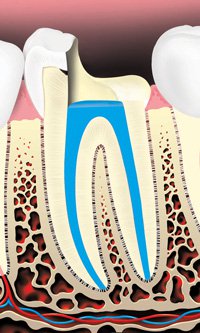

The root canals and pulp chamber are filled.

A metal or plastic rod or post may be placed in the root canal to help retain the core (filling) material, which supports the restoration (crown).

The tooth is then restored with a crown or filling.

rid of bacteria. - The root canals are usually filled with a rubber-like material to seal them.

- A temporary filling is then placed in the tooth to prevent contamination of the root canals. You might be given antibiotics if the infection has spread beyond the end of the root(s). If your dentist prescribes medicine, use it only as directed. If you have any problems with the medicine, call your dentist.

- During the next stage of treatment, the dentist removes the temporary filling and restores the tooth with a crown or a filling to strengthen it and improve the way it looks. If an endodontist performs the root canal treatment, he or she usually recommends that you return to your general dentist for this step.